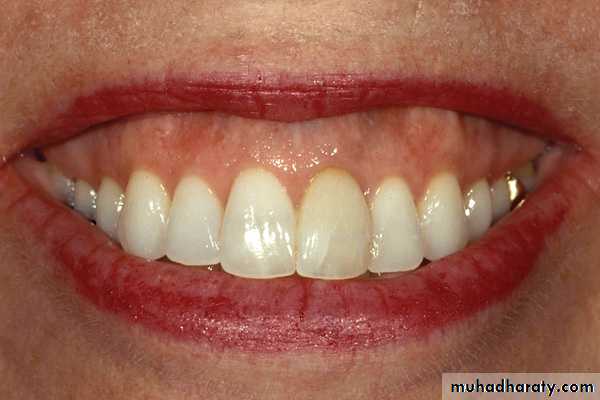

Lip length

How much tooth will be exposed ?

Determinant in anterior teeth selection.

Lip length is classified as -

A. Long B. Medium C. Short

lip line , smile line classification:

A high lip line

Low lip line

Normal lip line